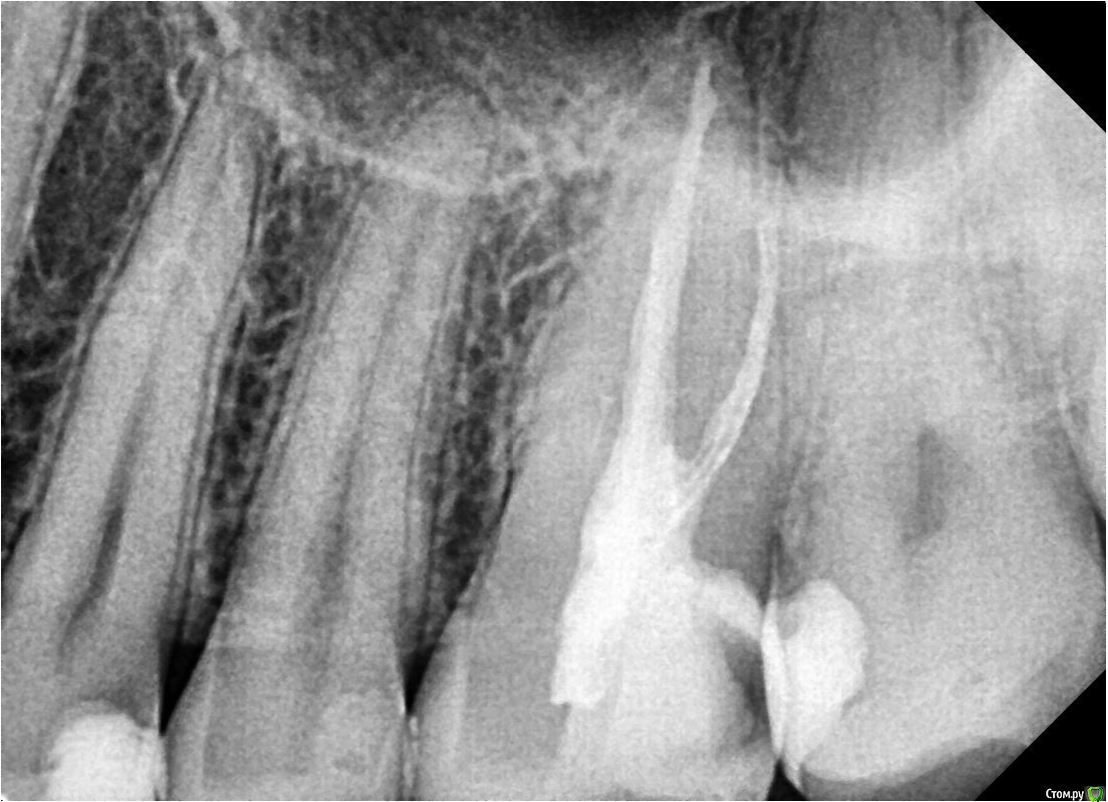

Liza544 Опубликовано 3 февраля, 2020 Поделиться Опубликовано 3 февраля, 2020 Добрый день.Помогите, пожалуйста, разобраться с причиной боли.Началось все приблизительно в начале октября (3 мес назад). Обратилась к стоматологу на проф осмотр, в ходе которого у меня обнаружили пульпит в 26-м зубе. В результате - удалили 3 нерва, но, со временем я обнаружила, что боль не прошла. Обходила несколько клиник. В ходе этого сделала пломбу на соседнем 25-м зубе. Совсем недавно удалила в том же 26-м зубе 4-й "маленький" нерв, так как сначала его не удалили, потому что не заметили (удаляла в клинике без микроскопа).В итоге, боль осталась прежней. Боль в области состыковки 26-го и 25-го зубов (при прикусывании на эту область). Наиболее логичными и вероятными предположениями, как по мне, являются: 1) 28-й зуб (зуб мудрости) , который у меня не удален - давит на соседние зубы и вызывает данную боль. Но, почему тогда, не болит 27-й? хотя, когда между 27 и 26-м провожу ниткой - есть кровь. 2) Воспалена десна. Один из стоматологов выразил данное предположение и в принципе оно может иметь место, так как когда вожу ниткой между 26-м и 25-м - болит десна. Но почему тогда так же болит и при надкусывании? К тому же, если в 26-м нету нервов, так как их удалили, как он вообще может болеть? Непонятно... Прилагаю снимки 25, 26, 27 и зуба мудрости.Буду очень признательна за хоть какие-нибудь предположения и комментарии. Спасибо. Ссылка на комментарий

Liza544 Опубликовано 4 февраля, 2020 Автор Поделиться Опубликовано 4 февраля, 2020 Вот еще пару снимков которые у меня есть. ПРошу заметить, что последние 4 снимка (файлы 7-10), которые я тут прикрепила - до пломбы на 25-м зубе и до залеченного 4-го канала в 26-м зубе. Подскажите пожалуйста, может ли быть зуб недостаточно залечен, хотя на КТ ничего подозрительного не видно? Ссылка на комментарий